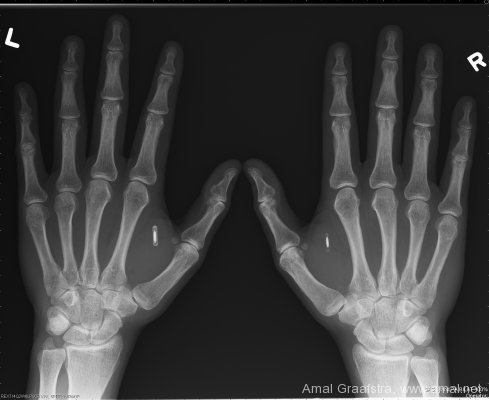

RFID Implant In X-Rays

Amal Graafstra